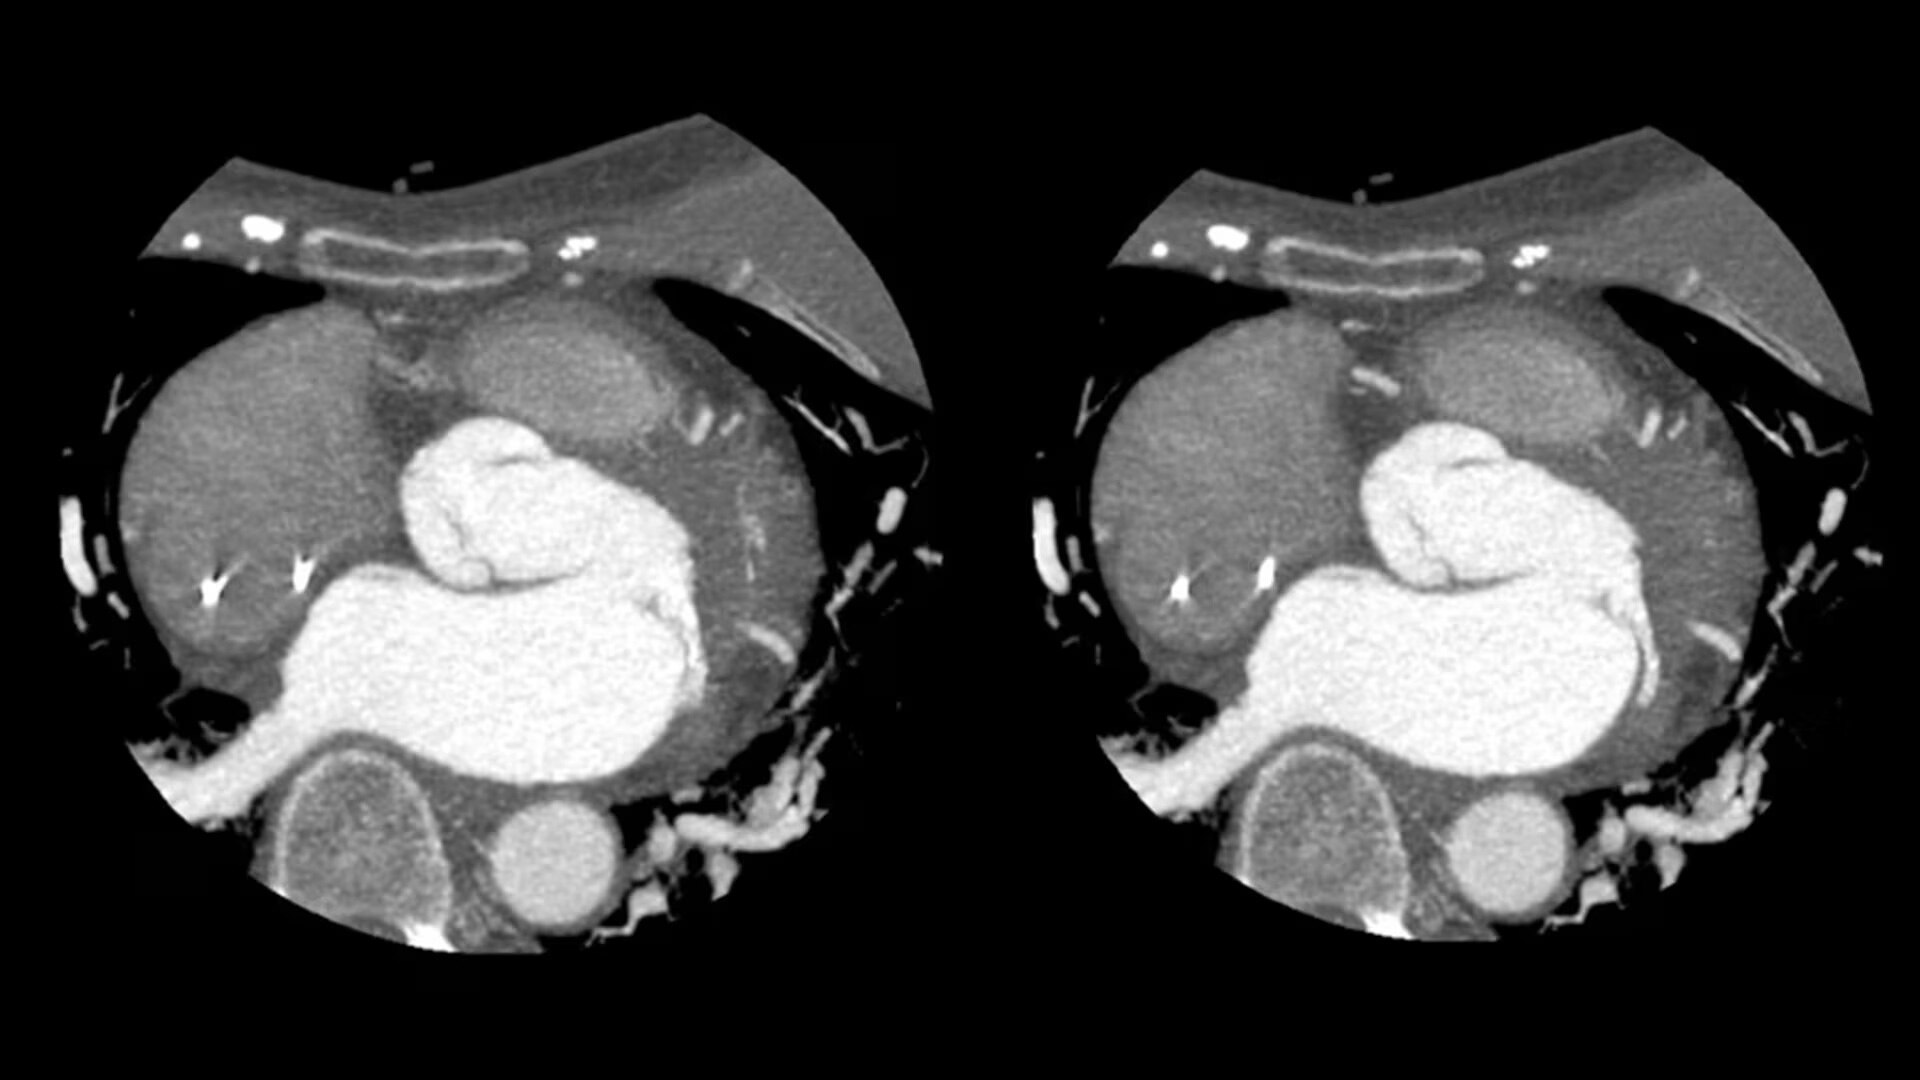

SnapShot Freeze 2

Intelligent and automated whole-heart motion correction for enhanced Cardiac CT imaging.

6x reduction in motion artifacts1

19.5 msec effective temporal resolution at 0.23s/rotation gantry speed2